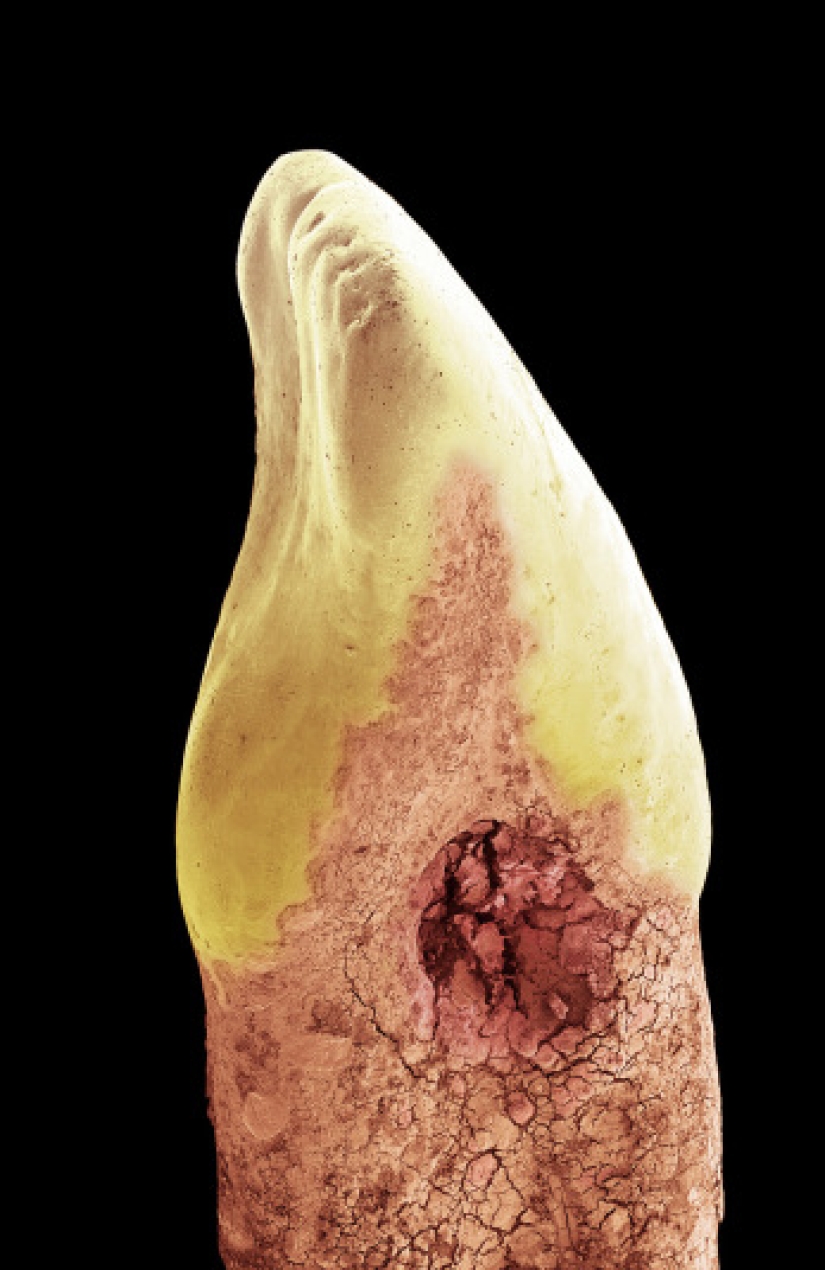

3. Diente de leche. La mayor parte del diente humano está formada por dentina, un sólido que envuelve la pulpa, que contiene vasos sanguíneos y nervios que solo se pueden ver cortando un diente o tomando un ortopantomograma (radiografía del diente). La corona del diente está cubierta de esmalte (la parte blanca del diente en la foto). El esmalte protege la dentina de los ácidos en la boca. La dentina en la raíz del diente está protegida por cemento radicular.

11. Diente de leche.